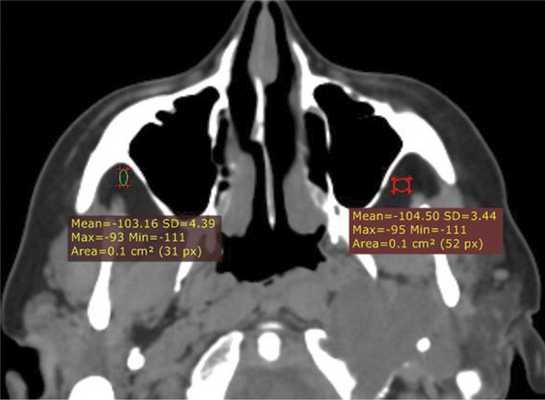

При воспалительных изменениях в ретроантральной жировой клетчатке верхнечелюстной пазухи на РКТ повышаются денситометрические значения ее плотности [10]. При одностороннем процессе отмечается выраженная асимметричность значений плотностей (рис. 4).

Рис. 4. Рентгеновская компьютерная томограмма околоносовых пазух. Аксиальная проекция, костное окно.

В 63,2% случаев на РКТ при выявлении одонтогенного верхнечелюстного синусита отмечалось уплотнение жировой клетчатки. Исследователи связывают это с переходом воспалительной инфильтрации пристеночной слизистой по периваскулярным пространствам к ретромаксиллярной клетчатке [7, 11, 12].